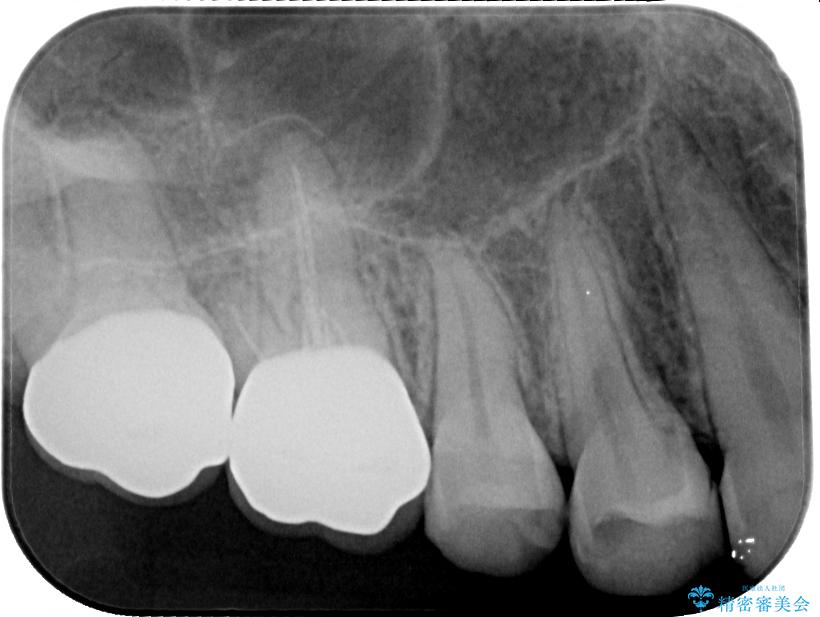

インプラント希望部位は右下第一大臼歯と第二大臼歯です。

しかし、噛み合わせの相手である右上の第二大臼歯が、長期間噛み合う歯がなかった影響で**挺出(歯が下に伸びてくる状態)してしまっており、このままではインプラントを埋入して被せもの(上部構造)を入れるためのスペースが不足している状態でした。

そこで、右上の奥歯に部分的なワイヤーを装着し、さらに矯正用アンカースクリュー(TADs)を併用することで、挺出した歯を圧下(歯を元の高さに戻す動き)させ、下顎にインプラントを埋入するための十分な垂直的スペースを確保しました。

スペースが整った段階で、右下の第一大臼歯と第二大臼歯にインプラントを埋入。

その後、挺出していた右上第一大臼歯と第二大臼歯に装着されていた銀歯についても、審美性と適合性の向上を目的に、オールセラミッククラウンにやり替えました。